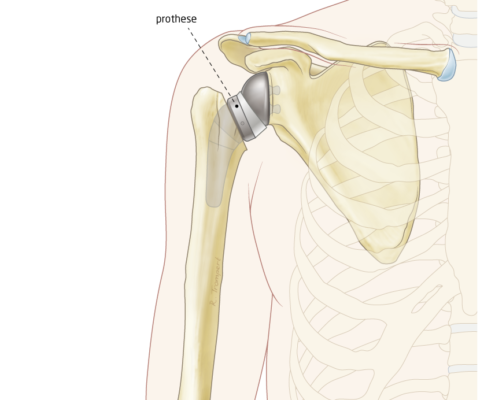

Reversed kop-kom prothese

Dit is een bijzondere constructie die steeds vaker wordt uitgevoerd met goede resultaten: kop en kom worden omgedraaid. De orthopeed maakt van de kop nu een kom en andersom. Het is wel een gewrichtsvervangende prothese.

Deze operatie wordt vaak gedaan als de schouderpezen niet meer goed werken. Je tilt na de operatie de schouder op aan de buitenste schouderspier, meestal met verbluffend goed resultaat.